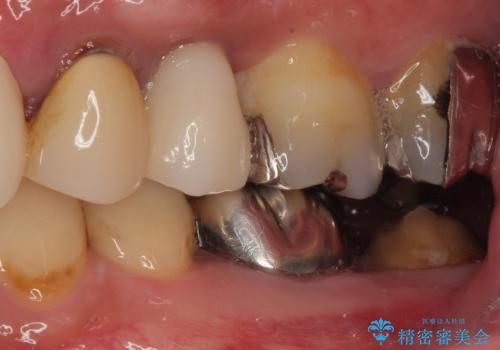

今回は、外科処置の回数を減らし、患者様の負担を最小限にするため、

**抜歯と同時にインプラントを埋入する「抜歯即時インプラント」**を選択しました。

抜歯と同時にインプラントを埋入し、その日のうちに仮歯を装着。

即日で審美性を回復できたため、治療当日から自然な見た目でお過ごしいただけました。